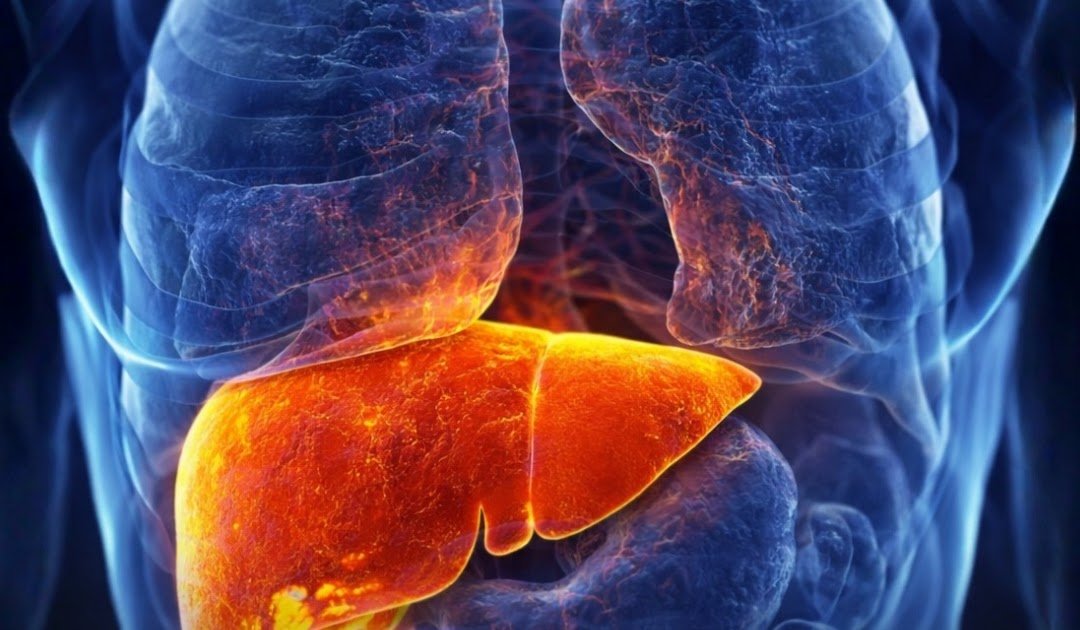

The liver is one of the hardest-working organs in the human body. It filters toxins, supports digestion, stores nutrients, and plays a key role in regulating fat and sugar metabolism.

But when overloaded by poor diet, excess calories, and sedentary habits, the liver can begin to store fat — a condition known as fatty liver disease (hepatic steatosis).

According to the World Health Organization, this silent condition affects nearly 1 in 3 adults worldwide, often without noticeable symptoms.